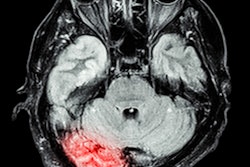

MRI indicates that people in early middle age with poor sleep quality show signs of poor brain health in the form of older brain age later in life, according to research published October 23 in Neurology.

"Sleep problems have been linked in previous research to poor thinking and memory skills later in life, putting people at higher risk for dementia," Cavaillès said. "Our study -- which used brain scans to determine participants' brain age -- suggests that poor sleep is linked to nearly three years of additional brain aging as early as middle age."

To address this knowledge gap, Cavaillès' group conducted a study that included 589 people with an average age of 40. Research participants completed sleep questionnaires at the start of the study and again five years later; they underwent brain MRI exams 15 years after the work began.

Study participants were slotted into three groups: A "low" group with no more than one poor sleep characteristic; a middle group with two or three; and a high group with more than three. At the start of the work, 70% of participants were in the low group, 22% in the middle group, and 8% in the high group. Cavaillès and colleagues assessed participants' brain scans, reviewing the level of brain shrinkage corresponding to age, and used machine learning to determine brain age for each person.

The investigators found that, after adjusting for age, sex, high blood pressure, and diabetes, people in the middle group had an average brain age that was 1.6 years older than those in the low group, and those in the high group had an average brain age that was 2.6 years older. Bad sleep quality, difficulty falling asleep, difficulty staying asleep and early morning awakening were associated with greater brain age, especially when these poor sleep characteristics manifested over a five-year period.